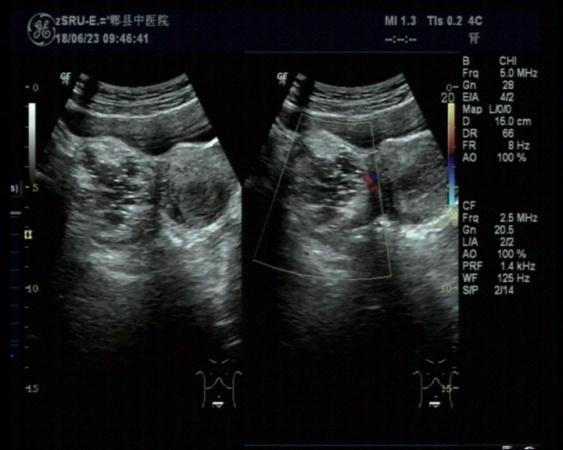

右侧附件区畸胎瘤可能

女,30岁,既往体检无异常,此次超声检查如图所示:右侧附件区探及一杂乱不均回声团,边界清楚,形态规则,CDFI:周边可见少许血流信号。